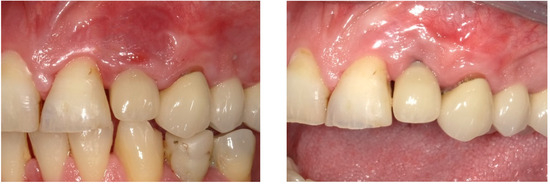

4. Timeline and Diagnostic Assessment

5. Therapeutic Intervention

6. Follow-Up